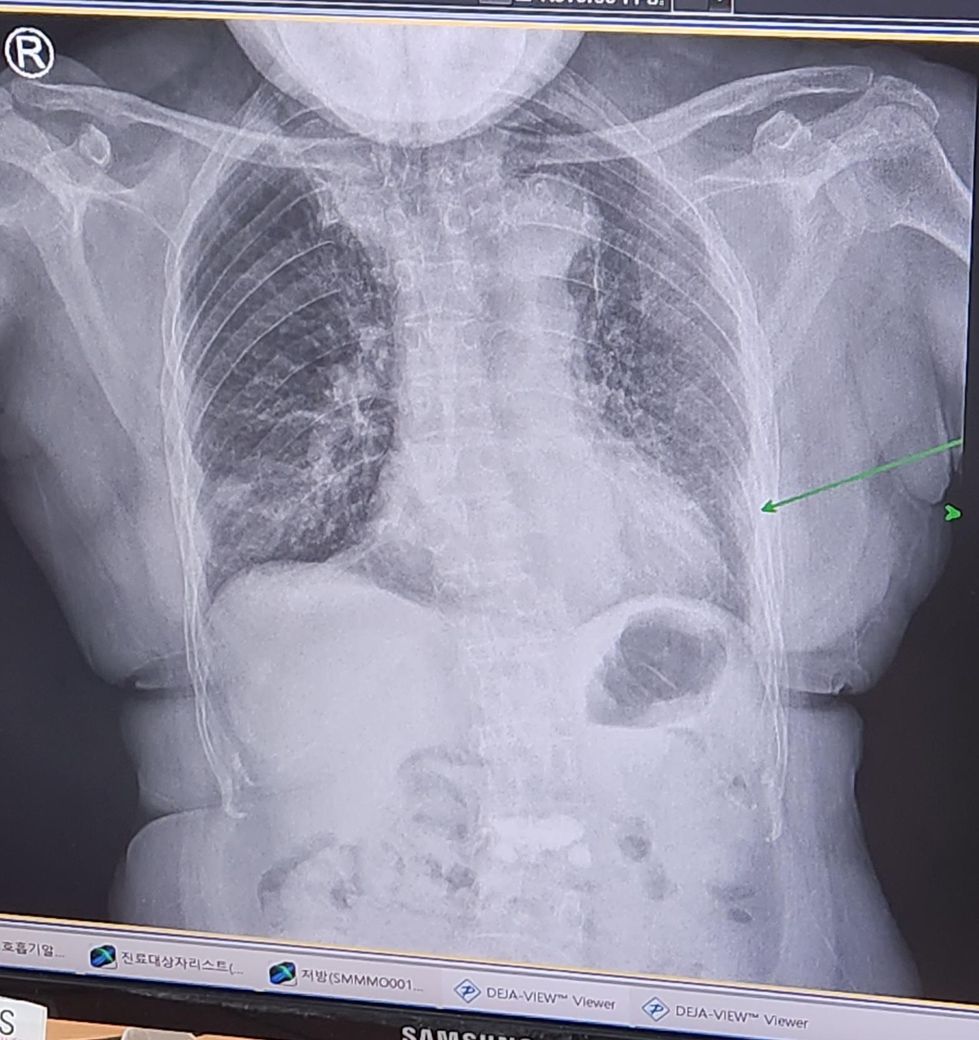

엑스레이상 염증이 아직 남아있는지

궁금하여 문의드립니다.

많이남아있나요?________

아래사진 첨부드립니다. 감사합니다

• 1번 째 사진

네 아직 남아있습니다. 정상 엑스레이는 아래와 같아요.

즉 보여주신 엑스레이에서 흰색 부분이 많이 보이는게 보이실 텐데 그게 폐렴을 나타내주는 겁니다.

다만 엑스레이 상태와 임상 중증도가 항상 일치하지는 않기 때문에 다른 수치들 (혈액검사 등)과 함께 증상도 고려해서 폐렴의 호전도를 결정하게 되는거에요

그래서 이런 모든 것들을 총체적으로 판단 할 수 있는 담당 의사와 상의 하시는게 제일 정확한거라 말씀드리는 거구요